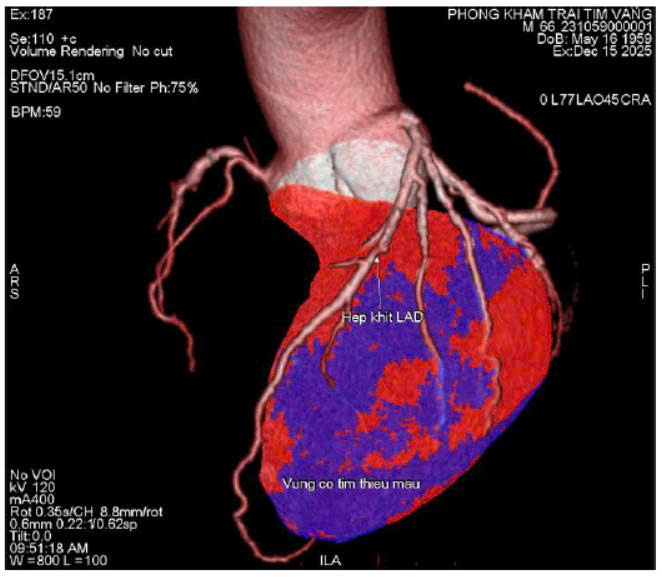

Nhiều bệnh nhân không có cơn đau tim rõ ràng, chỉ cảm thấy mệt, hụt hơi, tức ngực thoáng qua.

Tuy nhiên, khi kiểm tra chuyên sâu, bác sĩ phát hiện hẹp nặng động mạch vành LAD – nhánh mạch quan trọng nuôi tim.

- Khi mạch vành hẹp trên 70%, nguy cơ nhồi máu cơ tim tăng rõ rệt